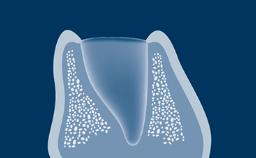

Um pré-requisito para o sucesso do tratamento com implantes é que o implante seja instalado com estabilidade primária e se integre com sucesso ao osso da arcada em uma posição predeterminada, direcionada pela prótese. Para a osseointegração do implante, é essencial que o osso vivo seja tratado com cuidado durante o procedimento de instalação do implante. Os clínicos, portanto, precisam entender a composição e a natureza do osso vivo antes de realizar procedimentos com implantes dentários.

Diante do requisito de se instalar implantes na posição correta determinada pelo planejamento protético prévio geralmente significa que há falta de volume ósseo para incorporar completamente o implante. Implantes que não são completamente cobertos por osso podem apresentar risco em uma variedade de complicações, incluindo recessão de tecidos moles, inflamação e infecção devido à colonização da superfície do implante exposto à biofilmes bacterianos e até a perda do implante devido ao suporte ósseo insuficiente. Procedimentos de enxerto para aumentar o volume do osso são frequentemente necessários para garantir que os implantes estejam completamente cobertos de osso. Este módulo descreverá a composição e a natureza do osso vivo, materiais de enxertia utilizados na implantodontia, bem como diferentes modos de cicatrização de diferentes enxertos.